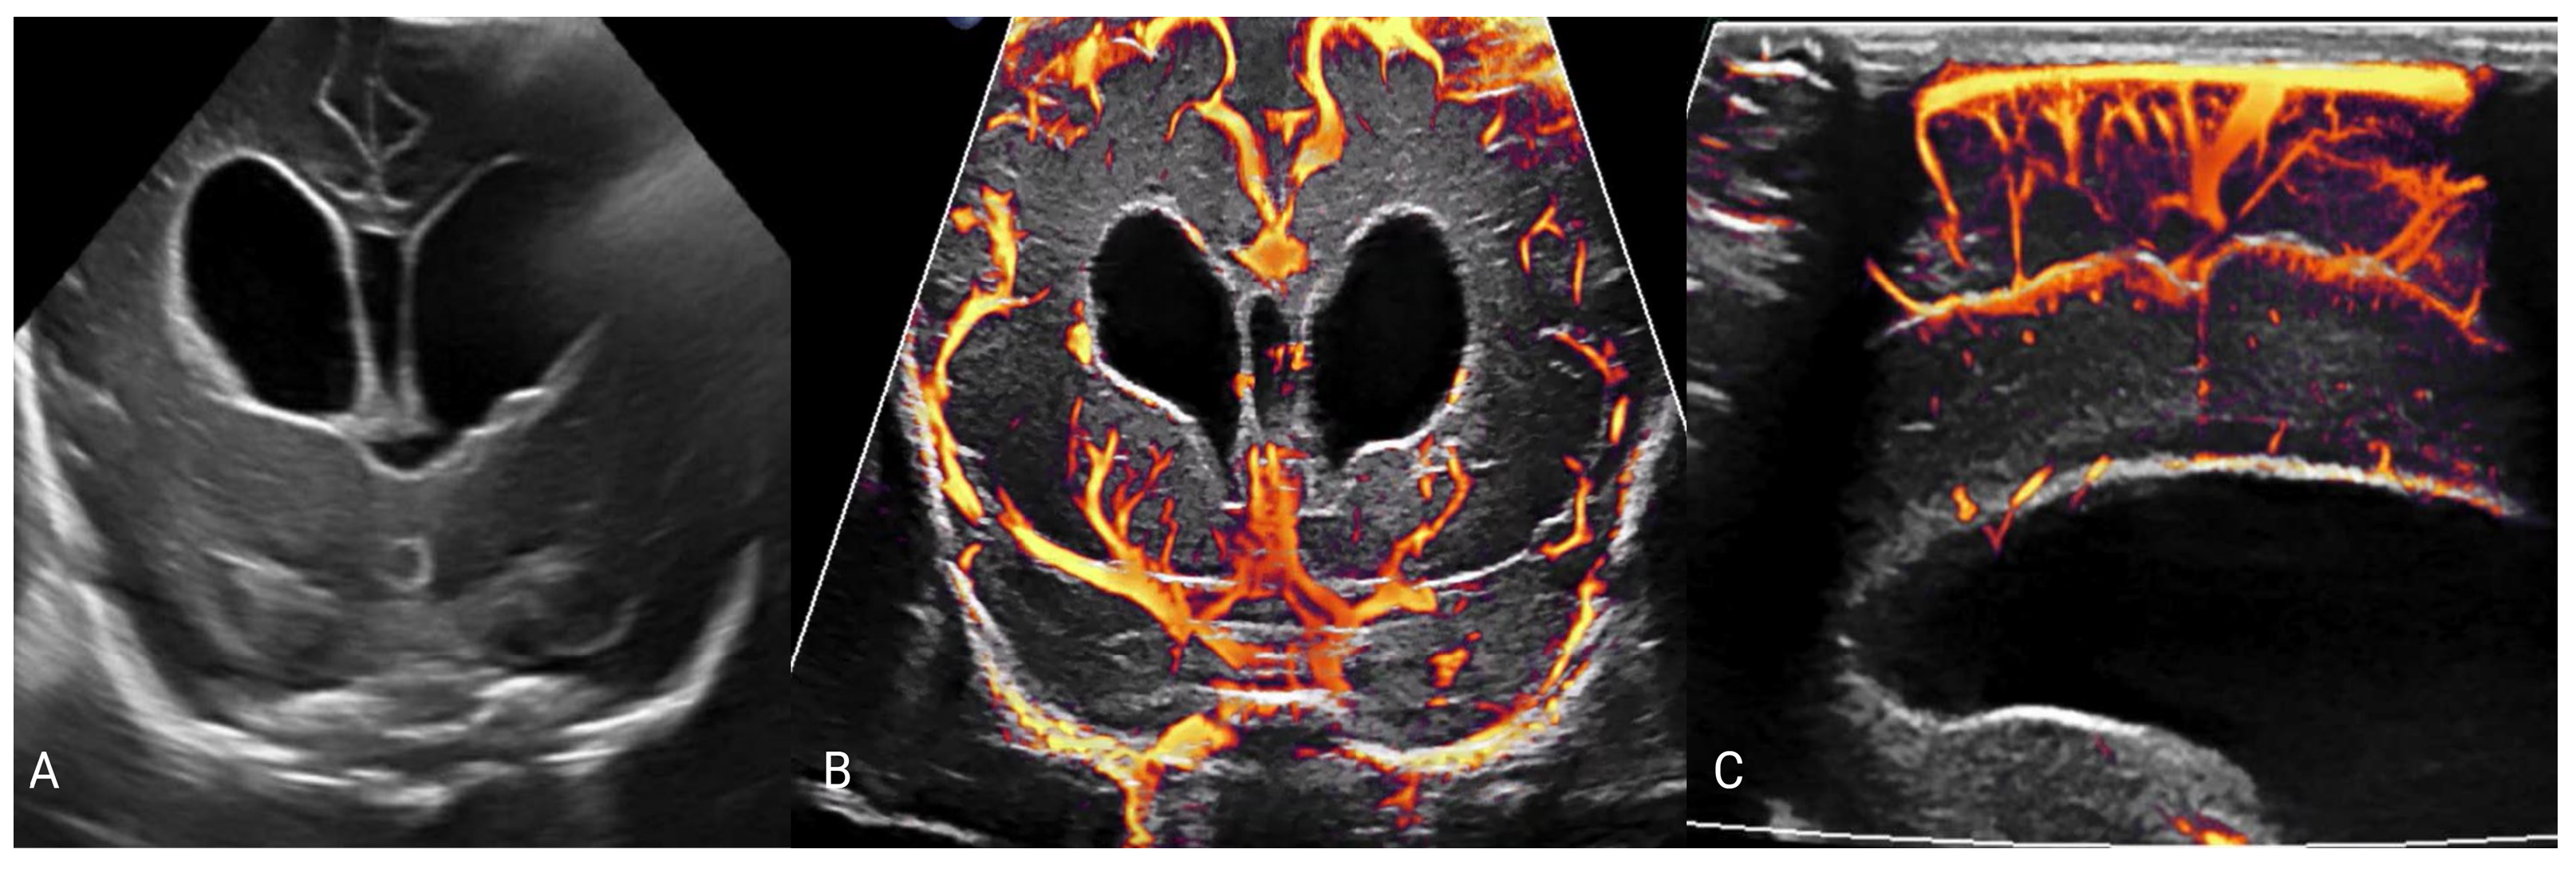

- Hwang, M.; Zhang, Z.; Katz, J.; Freeman, C.; Kilbaugh, T. Brain contrast-enhanced ultrasonography and elastography in infants. Ultrasonography 2022, 41, 633–649. [Google Scholar] [CrossRef]

- Barletta, A.; Balbi, M.; Surace, A.; Caroli, A.; Radaelli, S.; Musto, F.; Saruggia, M.; Mangili, G.; Gerevini, S.; Sironi, S. Cerebral superb microvascular imaging in preterm neonates: In vivo evaluation of thalamic, striatal, and extrastriatal angioarchitecture. Neuroradiology 2021, 63, 1103–1112. [Google Scholar] [CrossRef] [PubMed]

- Freeman, C.W.; Hwang, M. Advanced ultrasound techniques for neuroimaging in pediatric critical care: A review. Children 2022, 9, 170. [Google Scholar] [CrossRef] [PubMed]

- Couture, O.; Hingot, V.; Heiles, B.; Muleki-Seya, P.; Tanter, M. Ultrasound Localization Microscopy and Super-Resolution: A State of the Art. IEEE Trans. Ultrason. Ferroelectr. Freq. Control 2018, 65, 1304–1320. [Google Scholar] [CrossRef] [PubMed]